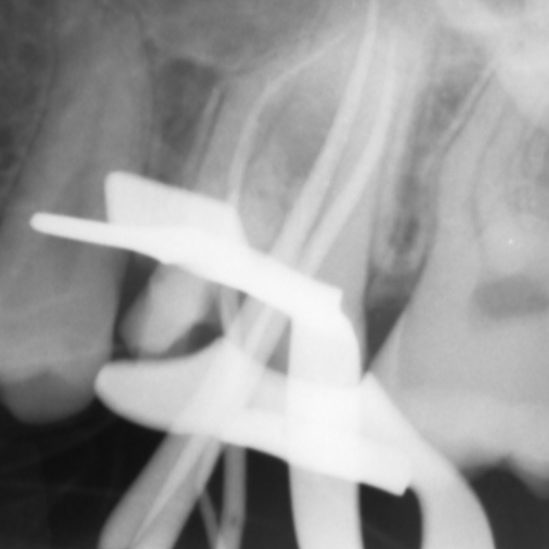

There are often multiple ports of communication between MB1 and MB2. The MB2 can join MB1 along its path or terminate via a separate apical foramen (Figures 1 and 2). Rarely, there can be an MB3 canal present (Figure 3).

Figure 1: MB1 and MB2 are two separate canals.

- Preoperative radiograph

- Mid-fill radiograph showing MB1 and MB2 are completely separate canals with individual apical foramen; both canals have acute apical curvatures

- Postoperative radiograph; a lateral canal was noted in the palatal canal.